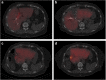

Methods: Nine patients with colorectal liver metastases treated with neoadjuvant chemotherapy and operated with ALPPS were studied with hepatobiliary scintigraphy, computed tomography, indocyanine green clearance test, and serum liver function tests. A comparison between liver volume and function was conducted.